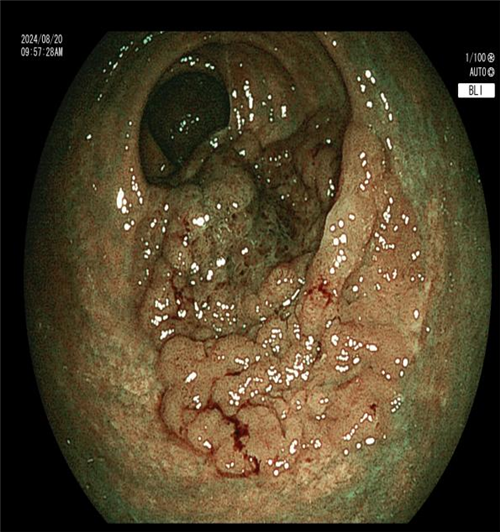

近日,一位患者因 “反复上腹胀痛、纳差 1 年余” 入住我院普外二科(胃肠外科)。入院肛检发现直肠后壁有大块颗粒样增厚区,CT 提示直肠壁增厚。进一步肠镜检查后,内镜下见直肠约 6*5cm 侧向发育型息肉,下缘距肛门仅 2.5cm,活检病理为绒毛状管状腺瘤。

科主任曾春辉在与患者及家属商讨手术方式时,了解到患者极度排斥外科手术,因其病变位置特殊,距离肛门仅 2.5cm,开刀恐难以保住肛门,患者表示宁愿不做手术也不愿生活质量低下。尽管病变巨大且位置特殊,内镜手术难度大、风险高,已超出常规 ESD 手术范畴,但曾主任毅然决定挑战技术极限。他在全麻下为患者施行 “内镜下直肠下段侧向发育息肉 ESD 术(隧道内镜技术)”,手术顺利完成。